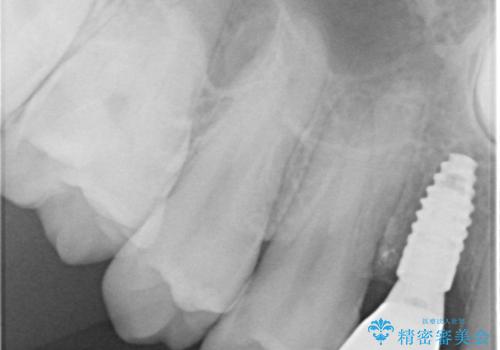

CT撮影を行ったところ、埋もれている犬歯を牽引して萌出させることは不可能と判断し、インプラントによる補綴治療を行うこととしました。

現在では、埋入時に仮歯を装着する「即時荷重インプラント」での取り扱いとなりますが、治療当時は未導入であったため、従来の複数回の外科処置を行う術式で治療を行いました。